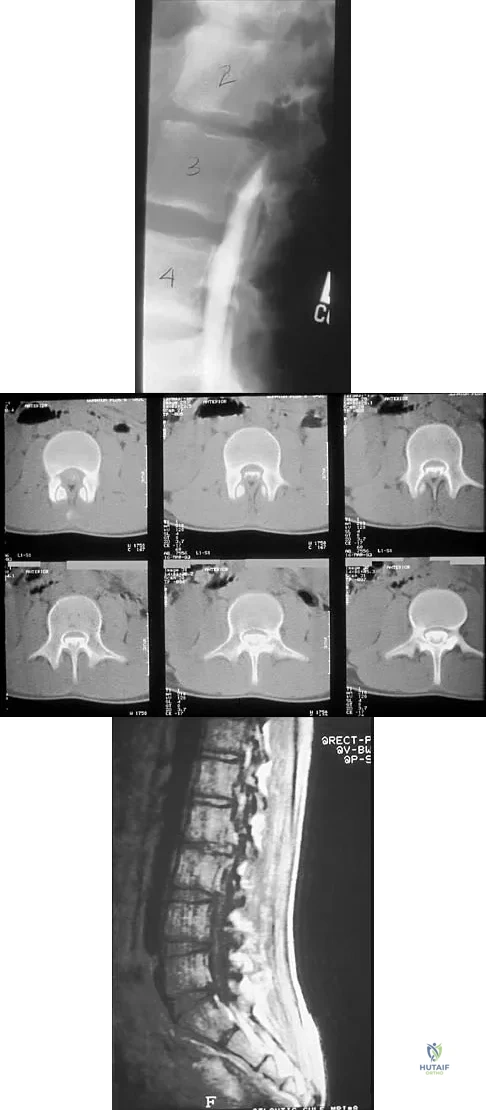

A 14-year-old football player has had thigh pain and weakness following a full-contact scrimmage 24 hours ago. He recalls that he felt a sharp pain in his back after colliding with a much heavier player. Examination reveals that the spine is minimally tender to palpation in the upper lumbar region. Motor testing reveals quadriceps weakness bilaterally, and a reverse straight leg raising test is positive. Plain radiographs of the thoracolumbar spine are normal. A myelogram, a CT scan with contrast, and an MRI scan are shown in Figures 41a through 41c. What is the most likely diagnosis?